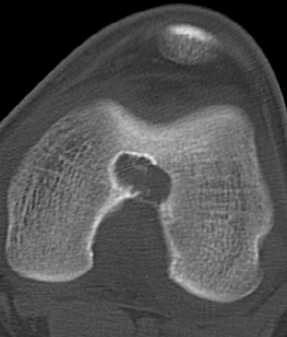

图 36.瘤软骨钙化:软骨母细胞瘤

图片

图 37.瘤软骨钙化:内生软骨瘤